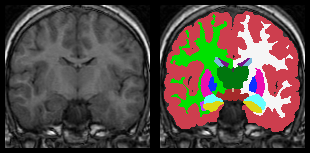

On a slightly different note, can any of these tools generate a

segmentation overlay (like the figure on the right in the attached

image)? Most of the colormaps I see supported in various

tools are scaled to statistical values (rather than strict

value-to-RGB that I really want); nilearn does appear to support an

unscaled colormap, but only on a single anatomical image (not a

segmentation overlay).